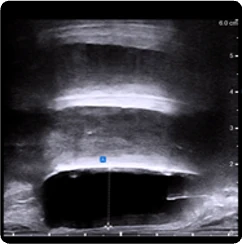

169 cc prostate ultrasound axial view showing BioProtect Balloon Spacer, prostate, and rectum.

Axial Ultrasound

Image courtesy of of Dr. Vishesh Agarwal, Radiation Oncologist.